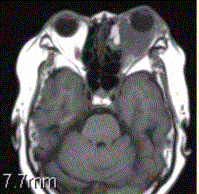

问题 患者女,64岁,左眼突出5年余。查体左眼球前突6mm,眼球运动自如,眼底无异常,下睑扪及边界不清、质软的肿块,视力正常,MR表现如下图。 诊为炎性假瘤,则此例患者的分型应为

选项 A.肿块型 B.弥漫炎症型 C.泪腺型 D.肌炎型 E.眼睑型 F.眼球型

答案 B